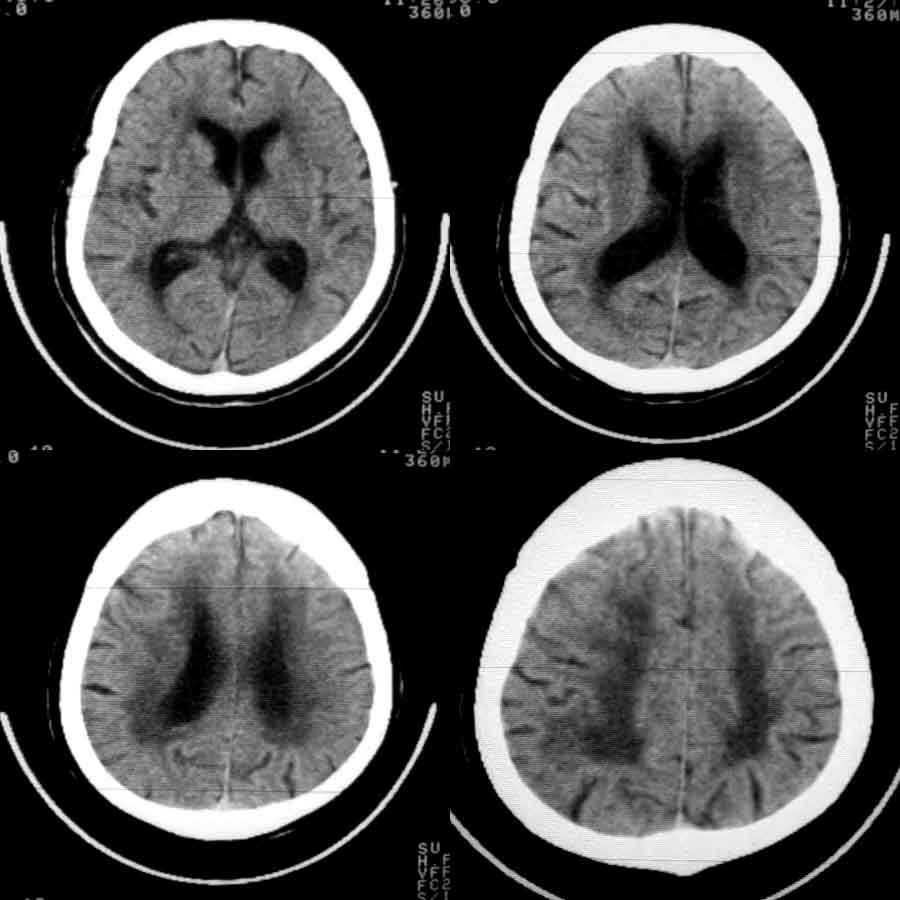

标题: CT8860:陈旧性脑出血 [打印本页]

标题: CT8860:陈旧性脑出血

女81岁,头晕、流延。

06年6月11日

06年6月24日

07年6月28日

时间已经一年,不可能是单纯血肿吸收,如果是应该是软化灶,周围不应该有环行高密度影,应该行增强扫描,看是否是肿瘤并出血,出血吸收,肿瘤存在,或后来合并炎症病灶.

1 皮层下动脉硬化性脑病伴脑萎缩(无争议)

2 左丘脑区脑出血吸收期改变(有争议),一年出血已吸收,应为软化,边缘环形壁可能是胶质增生所致。